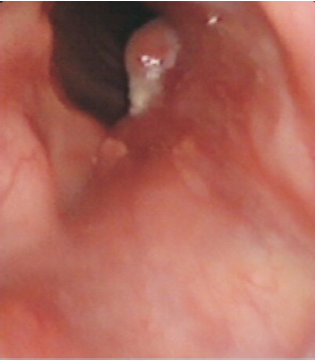

查体:PS=1分, 左侧声带全长及前联合处可见菜花样新生物、质韧, 双侧声带活动度可, 闭合不严, 发音嘶哑。全身浅表淋巴结未触及肿大。

颈部增强CT(2010-12-28):左侧声带小结节, 符合声门癌, 考虑累及前联合、右侧室带, 见图1。

入院诊断:左侧声门型鳞状细胞癌cT1bN0M0Ⅰ 期。